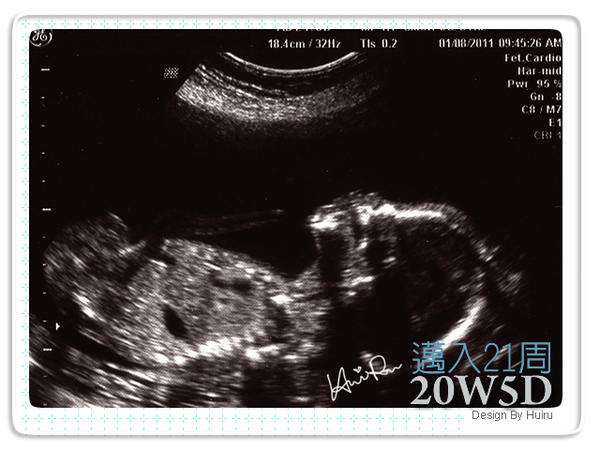

一邊趙她還會一直笑,因為好正的姿勢她說好好笑喔,好像再練軟骨功,腳竟然在頭的上面;過一會兒又看到好正的舌頭一直動一直動,她就說他在吐舌頭ㄟ,看來醫師比我還開心ㄟ,還細心的幫我標示一些位置。

超音波裡的好正腳丫子非常的明顯,好幾個角度都可以看到他的腳丫在那動來動去,就這樣醫師照了很久,阿不過連我中間跟她說我是來看吃壞肚子的,她還是持續幫我觀察,看她好熱心喔,我就不打擾她了><。(我躺到都快睡著了= =)